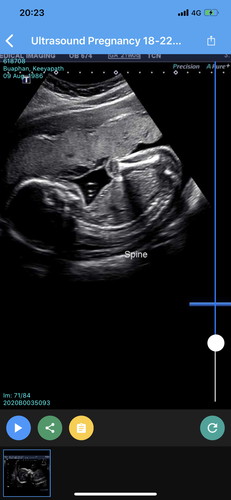

แม่ๆ ช่วยดูหน่อยได้ไหมคะ ได้น้องผู้หญิง หรือผู้ชายคะ น้อง 22 วีค

พอดีทีน้องที่ ออสเตรเลีย ไปซาวด์น้องมา จะมีเจ้าหน้าที่ซาวด์แยก มีคุณหมออ่านรีพอร์ตแยก แล้วค่อยส่งมาให้หมอประจำเราค่ะ คุณหมอบอกว่าน้อบแข็งแรงดี

รูปที่ 2 เหมือนจุ๊ดจู๋เลยค่ะ